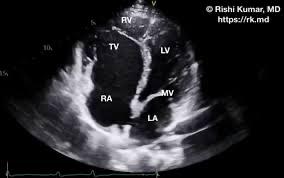

심초음파: 4가지 해부학적 이상을 모두 확인하여 확진

심초음파: 대혈관의 비정상적 연결을 확인하여 확진

심초음파: 우심방/우심실의 확장, 비정상적 폐정맥 연결 확인하여 진단

진단: 심초음파

심초음파: 진단